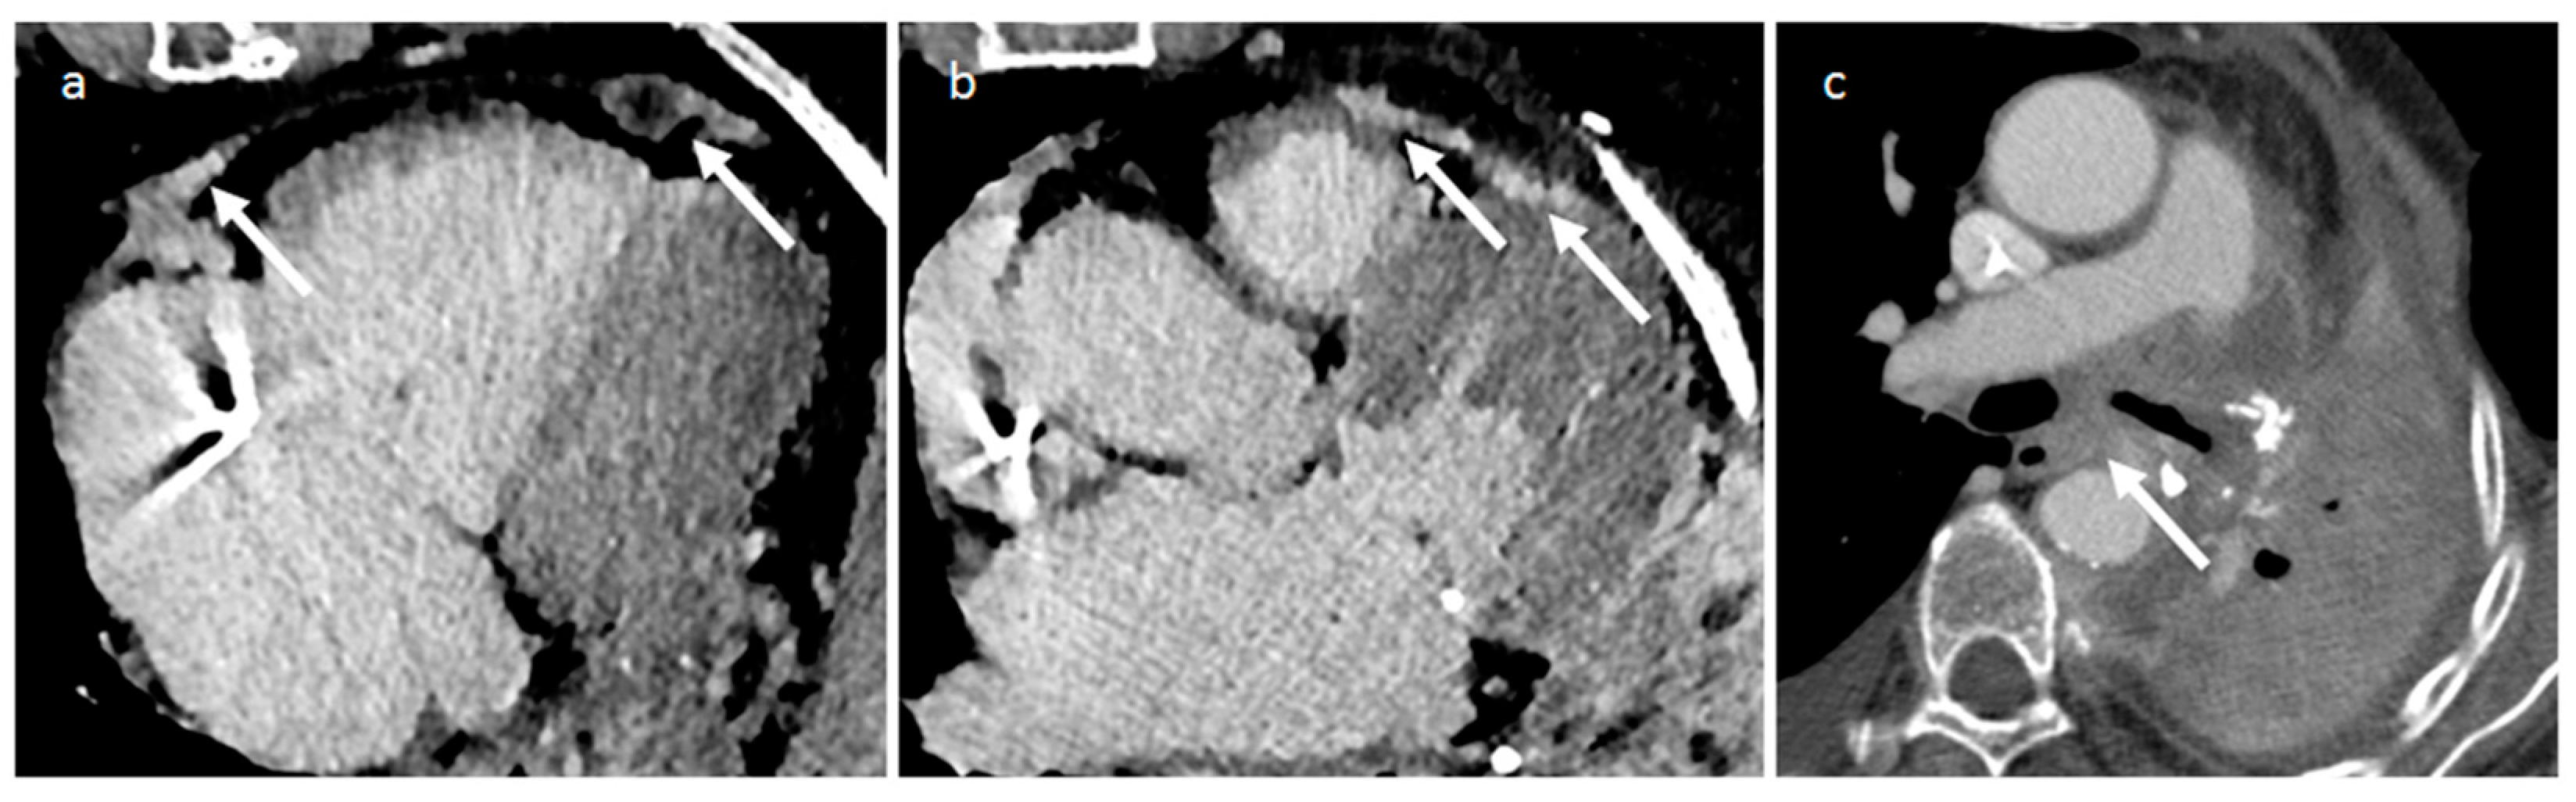

5.2. Primary Cardiac Sarcomas

| Angiosarcoma | Early and middle adulthood, Li-Fraumeni Sd | RA near AV sulcus, pericardium | Constitutional symptoms, heart failure, pericardial effusion | Vascular nature; hemorrhage and necrosis. Lung, liver and brain metastasis. | Iso-hyperechogenic and irregular mass, often as a nonmobile, broad-based, endocardial neoplasm with myocardial extension. Pericardial effusion | low-attenuation, irregular, intracavitary mass is often shown, pericardial thickening with effusion, heterogeneous enhancement | Heterogeneous Iso-hyper T1w, heterogeneous-hyper T2w, marked and heterogeneous enhancement and LGE. Perfusion imaging in the arterial phase shows immediate and strong enhancement |